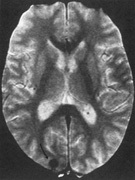

Fig. 10. Striate quadrantanopia. A. A 68-year-old woman with a stroke 3 years previously, causing left inferior quadrantanopia. B. MRI shows infarct of the superior bank of the right calcarine cortex.